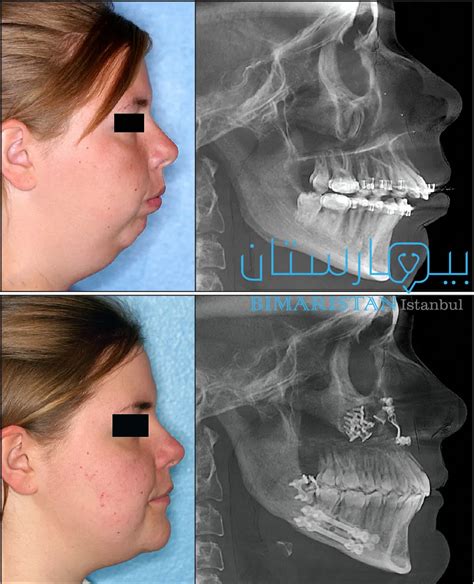

علاج انحسار الفك السفلي بدون جراحة

- إن الرجوع إلى طبيب أسنان متخصص هو أفضل طريقة لتحديد علاج انحسار الفك السفلي بدون جراحة.

- لأنه يعتمد على الفحوصات والأشعة السينية التي يقوم بها المريض والتي تبين العلاج المناسب لهذه الحالة.

- لكن غالبًا ما يكون تقويم الأسنان هو أفضل طريقة بالنسبة لنا لعلاج مشكلة تراجع الفك السفلي.

يتم تحديد كيفية إجراء تقويم الأسنان بعد تحليل مدى تراجع الفك أو تقدمه.

- عادة ما يحدد التقويم ما إذا كانت درجة الانحدار بين درجتين وأربع درجات.

- عند استخدام تقويم الأسنان في الحالات التي تكون درجة انحدارها أو تقدمها أكثر من أربع إلى ست درجات، فإنها عادة ما تصبح عديمة الفائدة ويصبح الحل الجراحي هو أفضل طريقة.